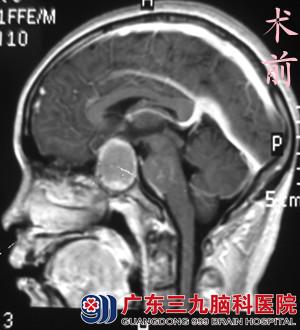

3个月前陆小姐无明显诱因出现双眼视物模糊,呈进行性加重,当地医院行头颅MR检查提示鞍区占位性病变。“不孕和这个肿瘤有关系吗……”陆小姐心里藏着许多疑问。

陆小姐来到广东三九脑科医院垂体瘤诊疗中心,经内分泌检查显示甲状腺功能及皮质醇均低下。经过替代性补充优甲乐及皮质醇类激素,复查内分泌结果基本正常。6月7日,由鲁明主任主刀,在全麻下行经鼻蝶胆脂瘤切除术,显微镜下见肿瘤组织呈黄白色,脂粉状,质地松,血供差,边界清楚,显微镜下予肿瘤切除,手术顺利结束。术后小陆经专科治疗,没有出现脑脊液漏、离子紊乱、尿崩等术后并发症,视力较术前明显好转,康复出院。术后病理结果为:胆脂瘤。

鲁明主任告知大家:鞍区位置的胆脂瘤常类似于垂体瘤,早期表现为视力减退、视野缺损等,甚至出现晚期视神经萎缩,但由于一般病情进展缓慢,视力严重减退和失明比较少见。亦可出现内分泌障碍,如性功能减退、多饮多尿等垂体功能不足及下丘脑损害症状。胆脂瘤属于良性肿瘤,多采取手术切除,术后恢复一般良好。对于曾接受手术治疗并病理确诊的患者,仍需要定期影像复查。